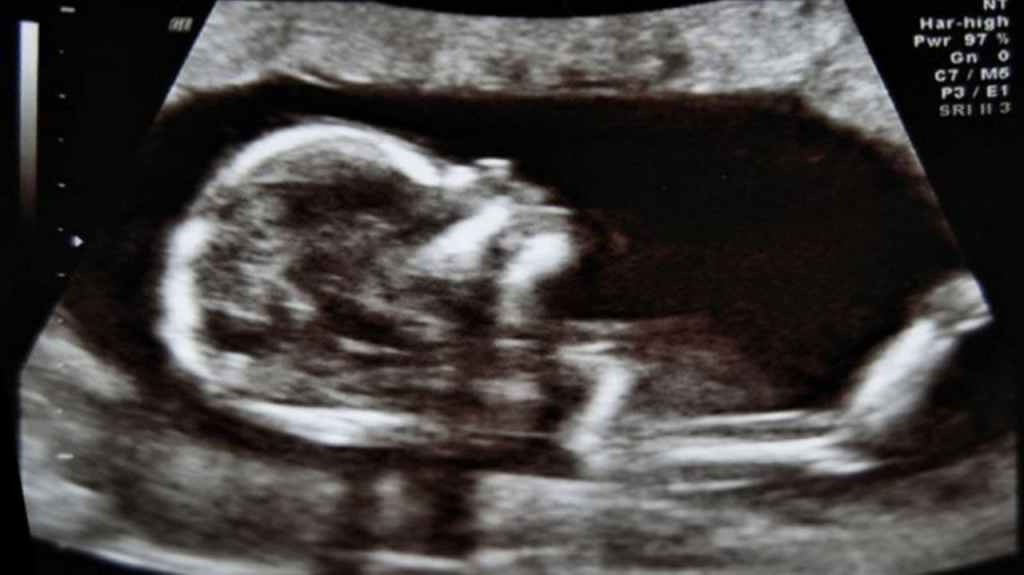

“Uno dei dati che più colpisce della débâcle pro-life avvenuta a San Marino in occasione del referendum sull’aborto è la percentuale degli astenuti: 59%. Sono loro ad avere vinto il referendum. […] La motivazione di fondo che ha portato all’astensione è probabilmente la seguente: il tema dell’aborto non interessa a nessuno. […] L’indifferenza nasce dal fatto che il fenomeno “aborto” è stato pienamente metabolizzato, perfettamente digerito. L’aborto non fa più problema. […] pochissimi in realtà sanno cosa è un aborto. E dunque moltissimi guardano un “quadro” che è un falso d’autore, assai edulcorato, dipinto con i colori dei diritti civili e dell’autodeterminazione della donna. Questi sono i “quadri” che hanno piazzato in casa nostra. Volete invece vincere un referendum sull’aborto? Mostrate il quadro autentico, fate vedere cosa è un aborto, piazzate sotto gli occhi del signor Rossi le carni straziate del bambino, dite a chi è favore dell’aborto che lui è a favore di quelle immagini. Fate gridare i bambini abortiti non con parole, ma con foto. Mostrate almeno un bambino nel ventre della madre. Allora sì che scuoterete le coscienze”